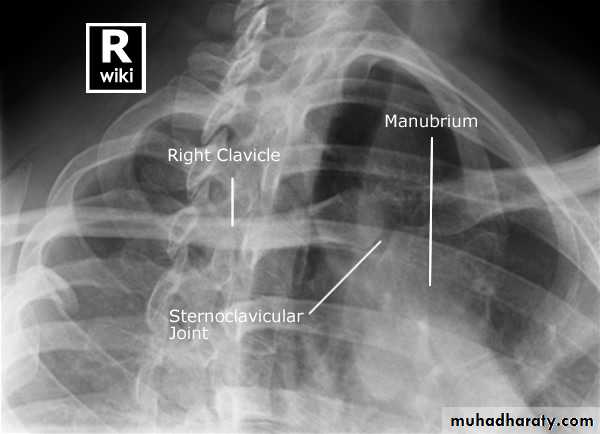

4-Sternoclavicular joint:

Adult Sternoclavicular Joints - PA Oblique